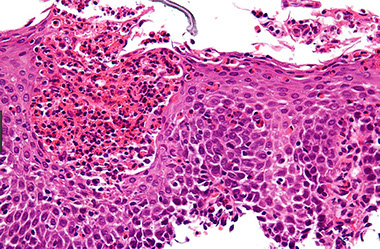

SCC composed of nests of malignant cells that partially recapitulate the organization of squamous epithelium